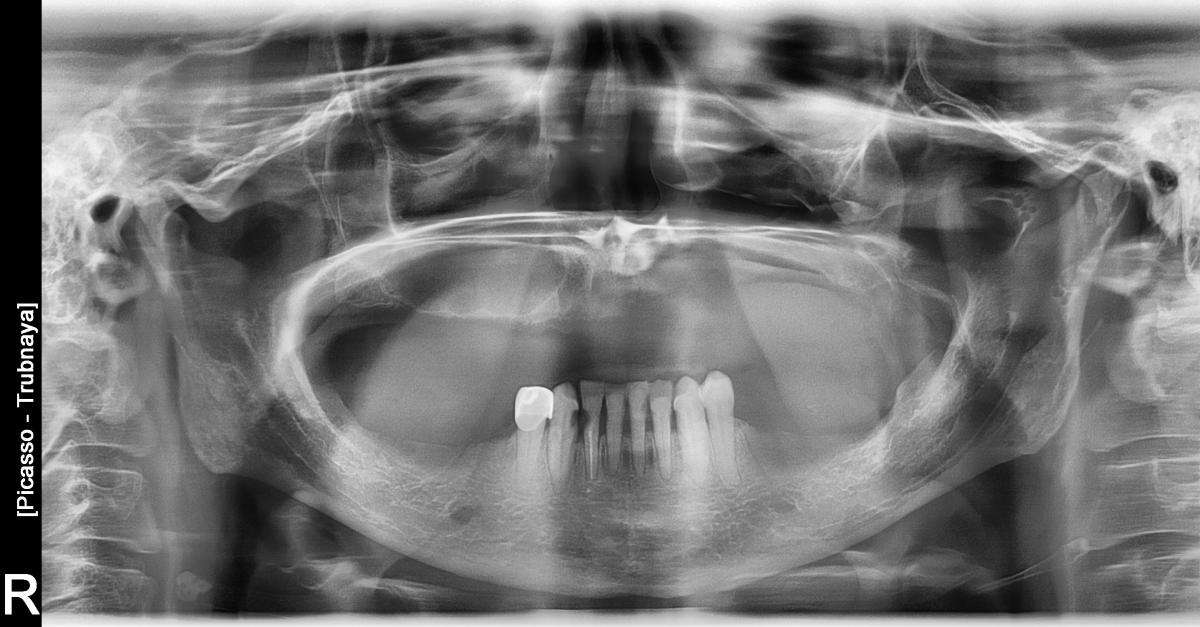

Рентгеновские снимки посттравматического остеомиелита челюсти: Медицинские случаи

Раздел: Образы вокруг